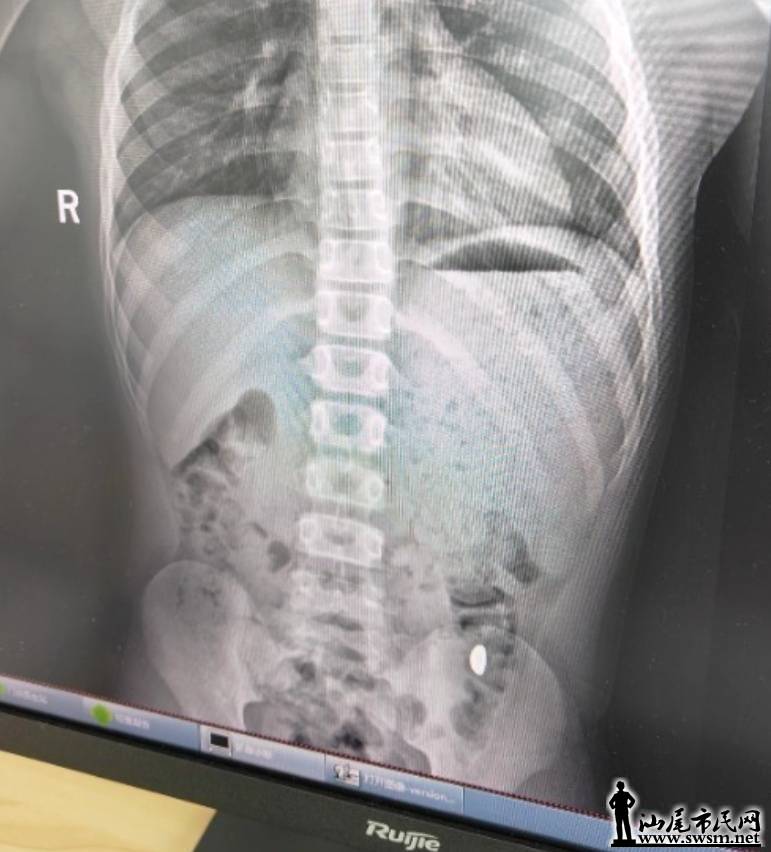

04fd24d60d0b4e5fa798cc869cf7d386.jpeg

右下加亮点为金豆。